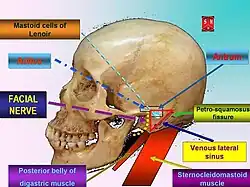

With prompt treatment, it is possible to cure mastoiditis. Seeking medical care early is important. However, it is difficult for antibiotics to penetrate to the interior of the mastoid process and so it may not be easy to cure the infection; it also may recur. Mastoiditis has many possible complications, all connected to the infection spreading to surrounding structures. Hearing loss is likely, or inflammation of the labyrinth of the inner ear (labyrinthitis) may occur, producing vertigo and an ear ringing may develop along with the hearing loss, making it more difficult to communicate. The infection may also spread to the facial nerve (cranial nerve VII), causing facial-nerve palsy, producing weakness or paralysis of some muscles of facial expression, on the same side of the face. Other complications include Bezold's abscess, an abscess (a collection of pus surrounded by inflamed tissue) behind the sternocleidomastoid muscle in the neck, or a subperiosteal abscess, between the periosteum and mastoid bone (resulting in the typical appearance of a protruding ear). Serious complications result if the infection spreads to the brain. These include meningitis (inflammation of the protective membranes surrounding the brain), epidural abscess (abscess between the skull and outer membrane of the brain), dural venous thrombophlebitis (inflammation of the venous structures of the brain), or brain abscess.[2][4]